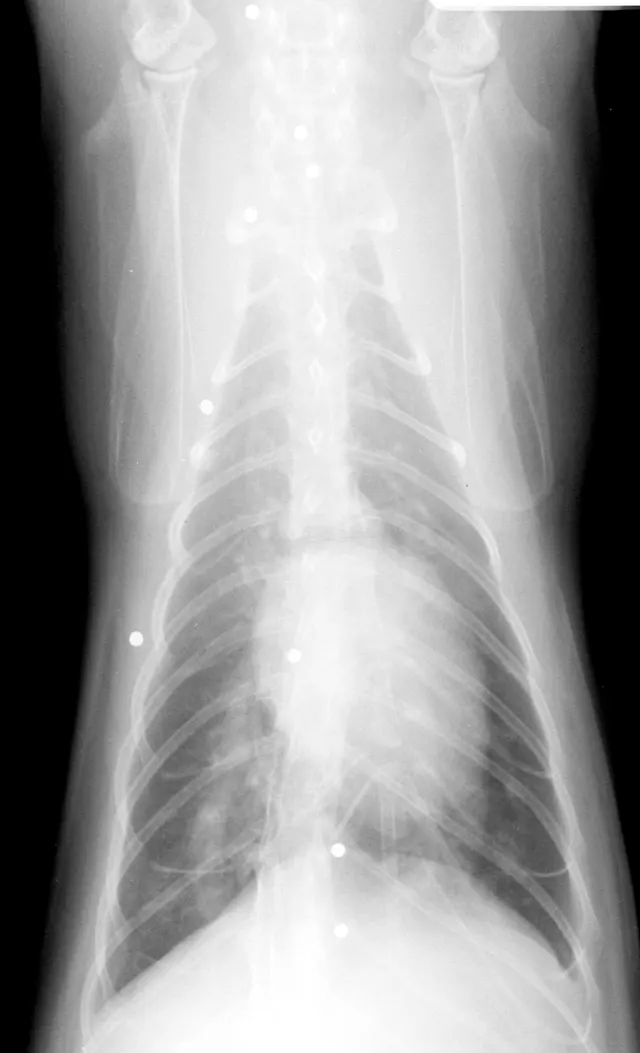

In addition to serologic tests, thoracic radiography and cardiac ultrasonography are important diagnostic tests in feline heartworm infection.

The cardiac silhouette of a cat with heartworms rarely has the "inverse D" appearance, or main pulmonary artery bulge, as seen in dogs. Cats more typically demonstrate radiographic findings compatible with feline bronchial disease ("asthma"). Nevertheless, certain findings, such as a caudal lobar pulmonary artery larger than 1.6 times the ninth rib at the ninth intercostal space, are quite suggestive of heartworm disease.